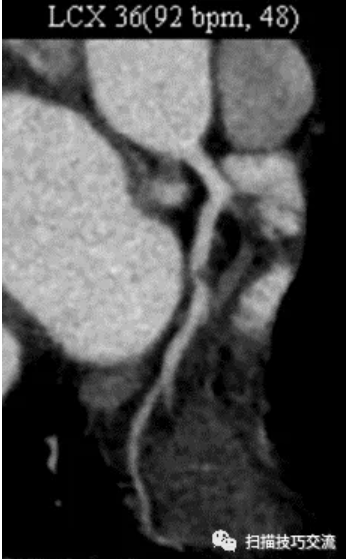

FIESTA电影,舒张期末 相同位置,并未发现脂肪高亮信号。 补充病史: 一、 CTA提示:LCX中段90%狭窄。 这与磁共振的MDE序列相吻合。